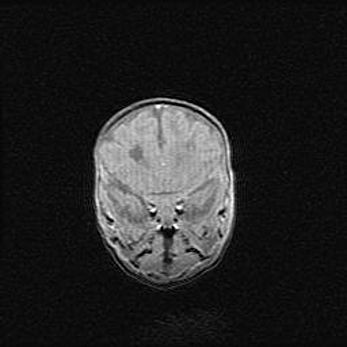

Неполная лизэнцефалия (пахигирия). Открытая гидроцефалия.

Возраст: 17 дней

Вес: 3110 г

Пол: мужской

Окружность головы: 33,5 см

Срок гестации: 35-36 недель

Лизэнцефалия—недоразвитие корковой пластинки и мозговых извилин в результате нарушения миграции нейронов коры. Поверхность мозговых полушарий гладкая. Микроскопически выявляется отсутствие нормальных слоев коры и скопление групп нейронов в подкорковом белом веществе.

Пахигирия—уменьшение числа вторичных извилин. В пораженном полушарии нервные клетки образуют толстый недифференцированный слой с неправильно расположенными нервными волокнами и группами гетеротопных клеток. Нервные клетки незрелые. Белое вещество истончено. При этом нередко аномально развит корково-спинномозговой путь.